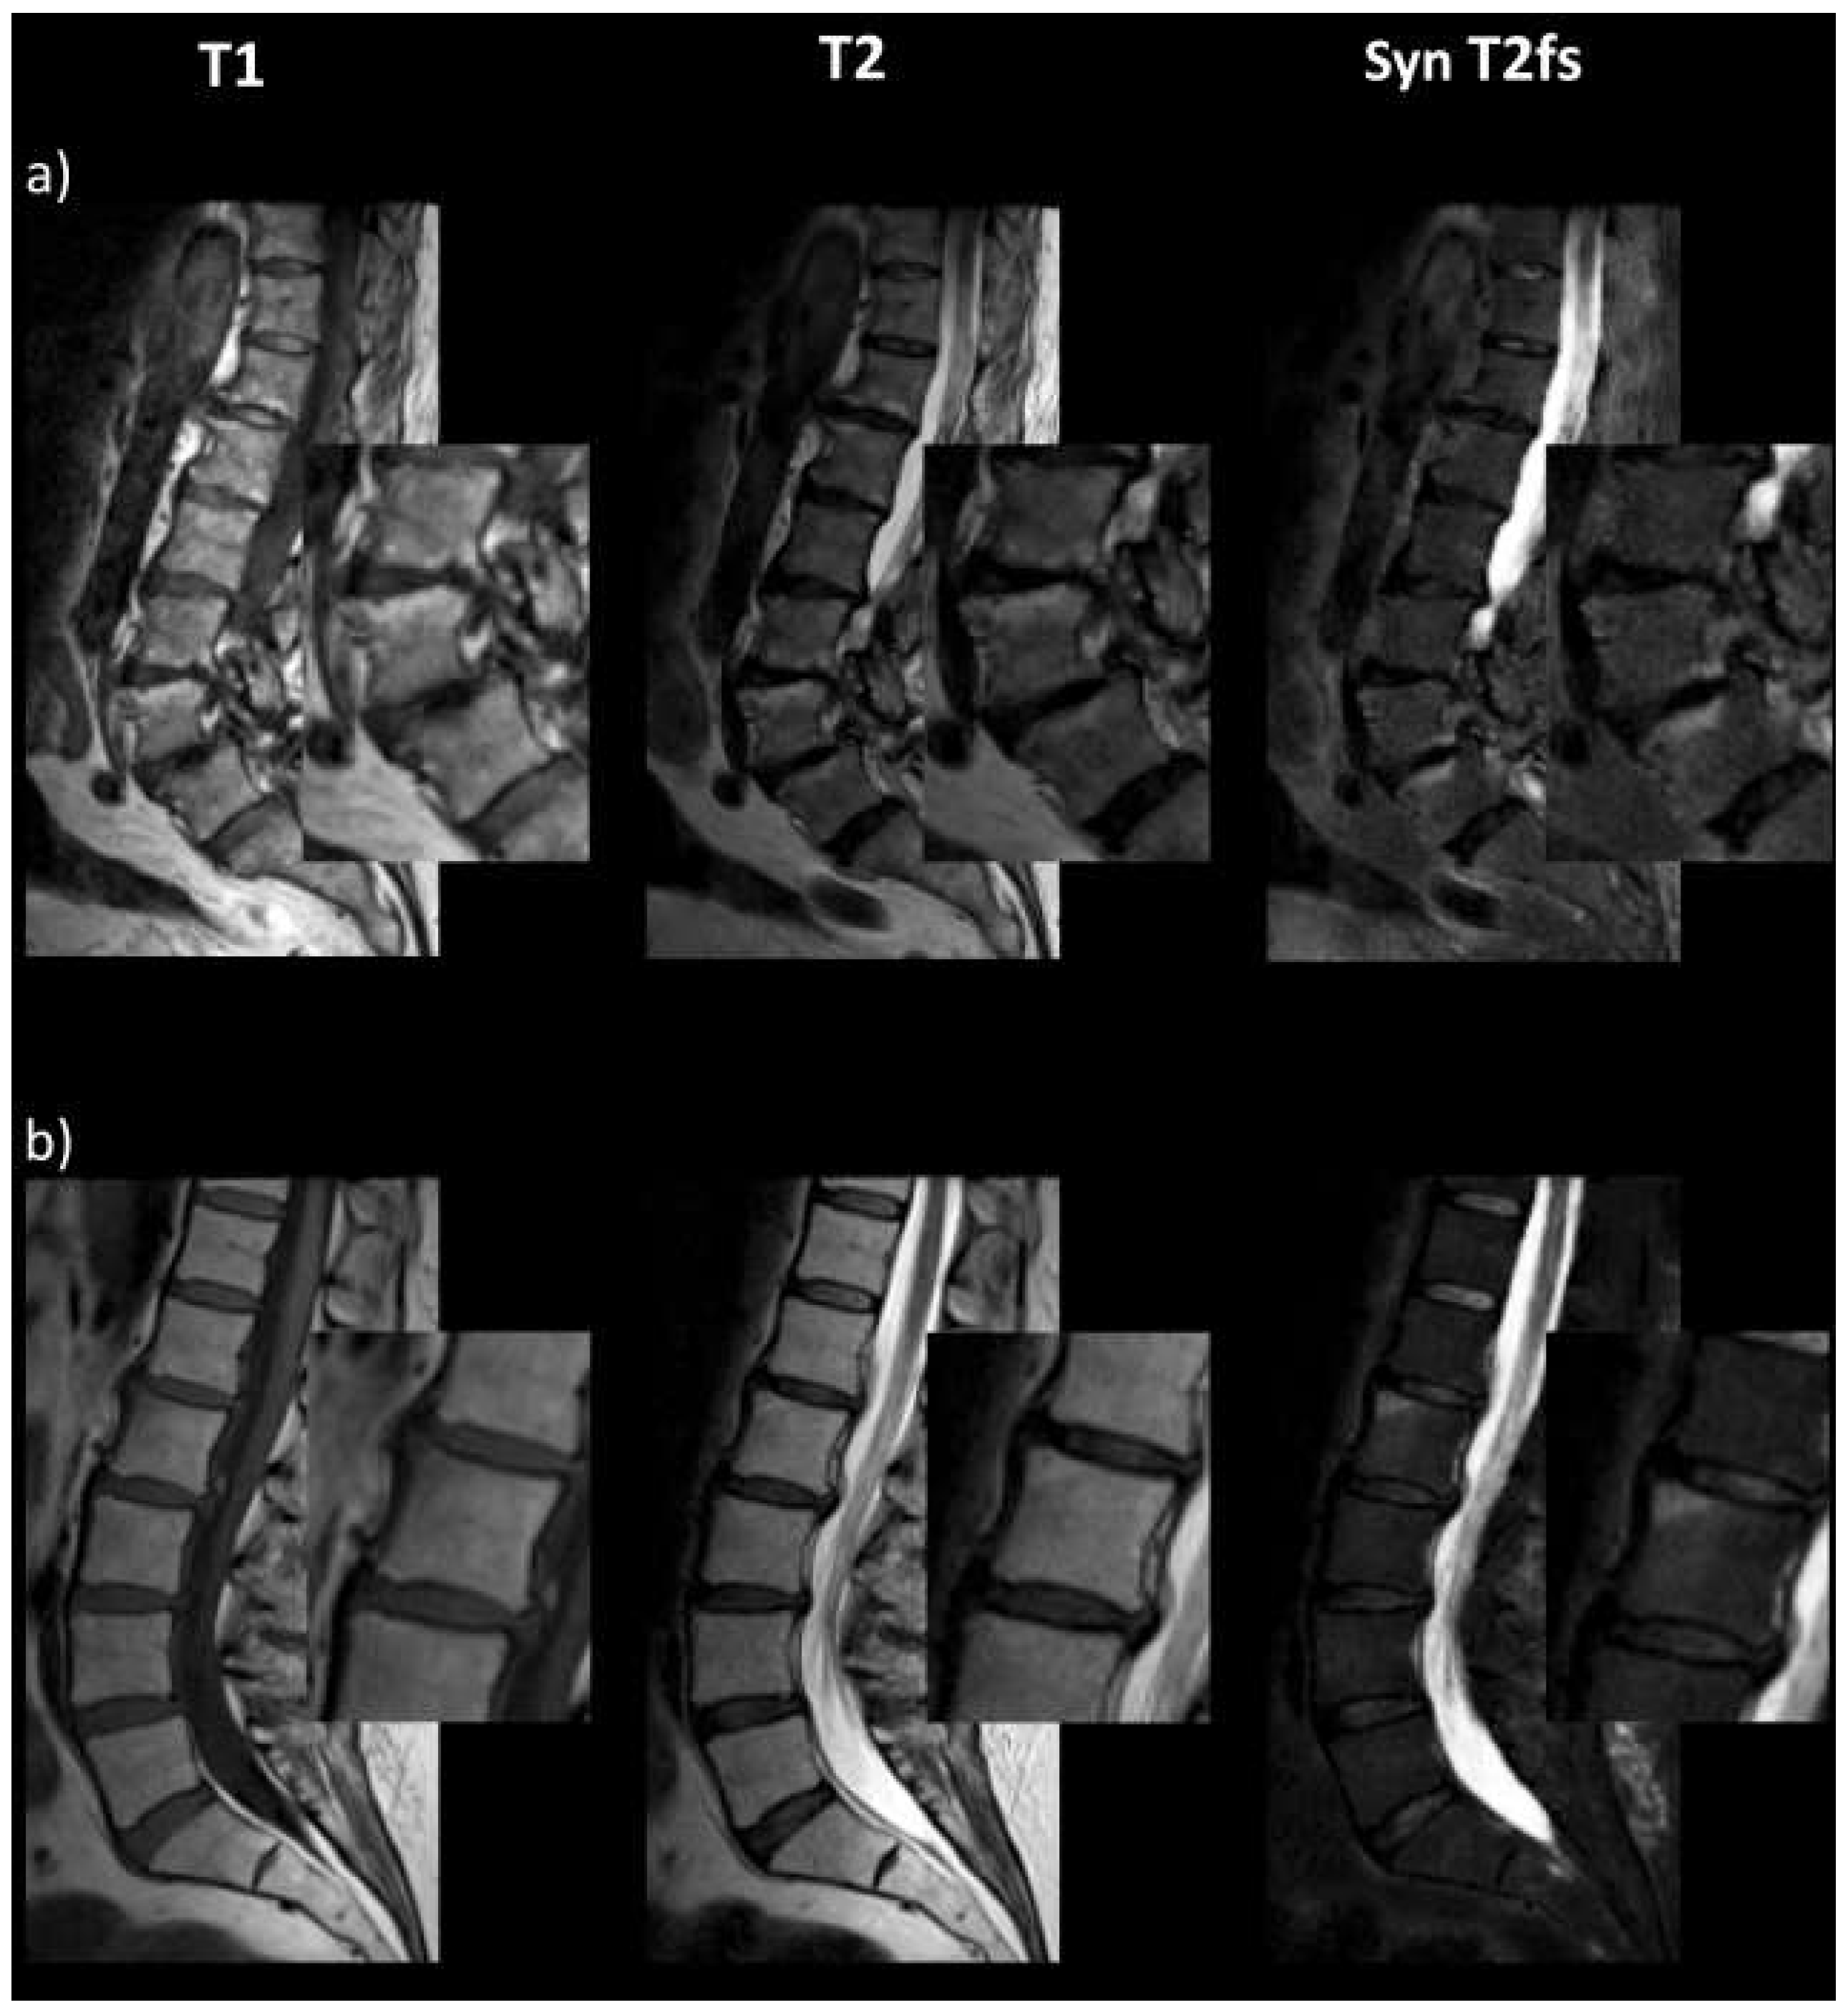

- Haubold, J.; Demircioglu, A.; Theysohn, J.M.; Wetter, A.; Radbruch, A.; Dörner, N.; Schlosser, T.W.; Deuschl, C.; Li, Y.; Nassenstein, K.; et al. Generating Virtual Short Tau Inversion Recovery (STIR) Images from T1- and T2-Weighted Images Using a Conditional Generative Adversarial Network in Spine Imaging. Diagnostics 2021, 11, 1542. [Google Scholar] [CrossRef]

- Kim, S.; Jang, H.; Jang, J.; Lee, Y.H.; Hwang, D. Deep-learned short tau inversion recovery imaging using multi-contrast MR images. Magn. Reson. Med. 2020, 84, 2994–3008. [Google Scholar] [CrossRef] [PubMed]

- Fayad, L.M.; Parekh, V.S.; de Castro Luna, R.; Ko, C.C.; Tank, D.; Fritz, J.; Ahlawat, S.; Jacobs, M.A. A Deep Learning System for Synthetic Knee Magnetic Resonance Imaging: Is Artificial Intelligence-Based Fat-Suppressed Imaging Feasible? Investig. Radiol. 2021, 56, 357–368. [Google Scholar] [CrossRef]

- Kim, S.; Jang, H.; Hong, S.; Hong, Y.S.; Bae, W.C.; Kim, S.; Hwang, D. Fat-saturated image generation from multi-contrast MRIs using generative adversarial networks with Bloch equation-based autoencoder regularization. Med. Image Anal. 2021, 73, 102198. [Google Scholar] [CrossRef]